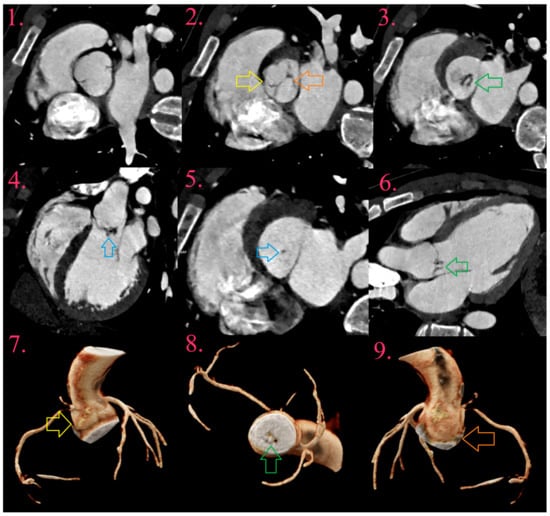

7.1. Abscess

7.2. Pseudoaneurysms

7.3. Fistula